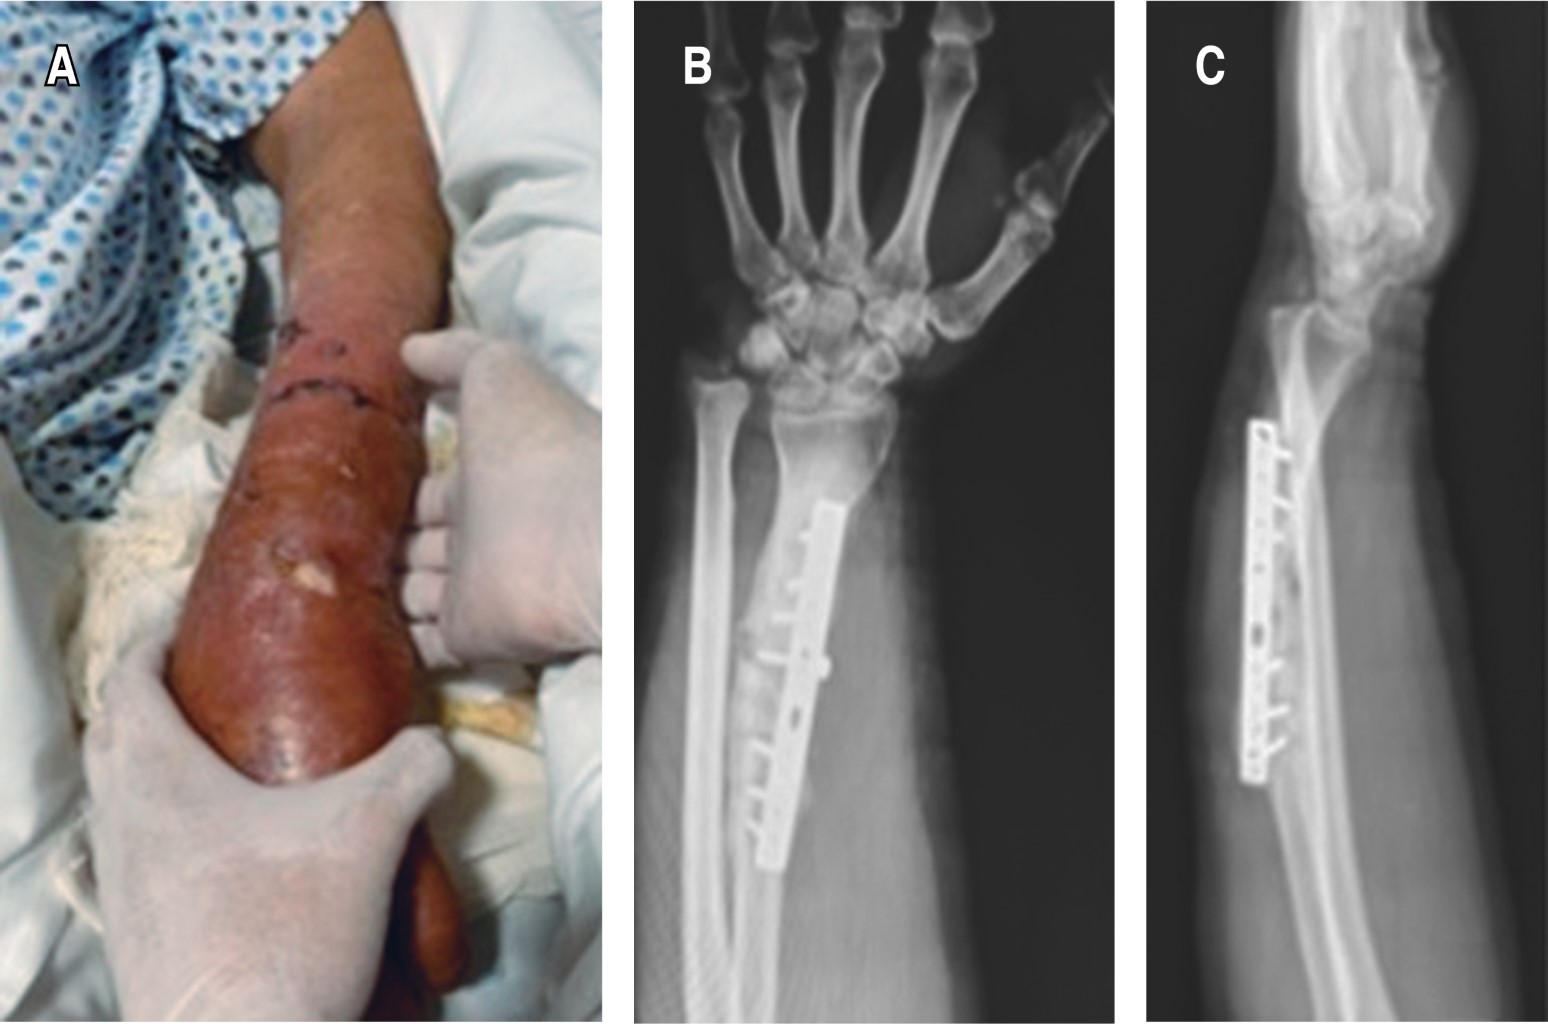

Gracias al seguimiento del paciente a uno, dos, tres, seis, ocho, 10 y 12 meses se obtuvo evolución satisfactoria tanto clínica como radiográficamente. Apreciamos puentes óseos en los extremos del aloinjerto de cresta a partir del tercer mes, por lo que se indicó rehabilitación con ejercicios isométricos, con carga parcial progresiva, mejorando la formación del callo óseo en el control a los seis meses, por lo que se indicó trabajo normal de la extremidad. Observamos regeneración ósea total a los 10 meses (Figura 4). En la actualidad el paciente se encuentra con función de extremidad conservada con una puntuación de 100 puntos en la escala modificada de muñeca de mayo.14

En este caso clínico podemos observar que ante una pérdida ósea en radio de 7 cm infectada por Pseudomonas aeruginosa en un inicio erradicamos la infección con la técnica Masquelet y posteriormente utilizando el concepto diamante logramos una consolidación completa a los 10 meses de evolución y 100 puntos en la escala funcional modificada de muñeca de mayo.